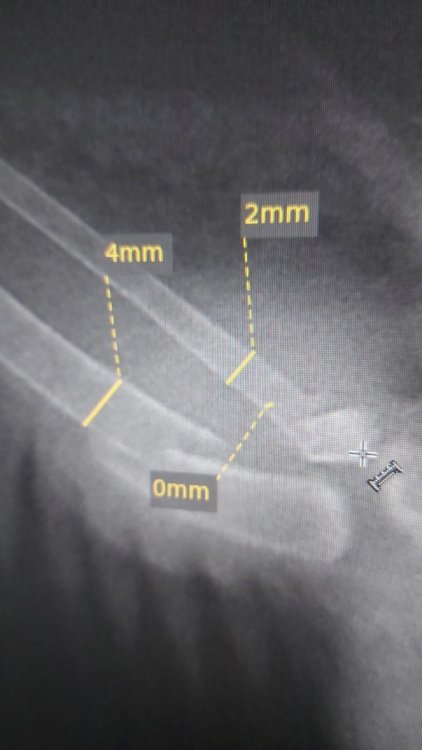

spring__rain@mail.ru Опубликовано 15 июня, 2022 Автор #8 Опубликовано 15 июня, 2022 10 часов назад, Шер Ами сказал: Вроде кости незадеты, значит цефтриаксон ненужен. Запох есть неприятный от раны? При открытой ране, если это мягкие ткани, то энрофлоксацин /ветеринарный/ вполне подойдёт. параллельно антибиотику Флуконазол /50 мг./ упаковку купить. @spring__rain@mail.ru кости задеты? Или это рана на мышцах? вроде нет запаха, но у меня с обонянием проблемы, я могу и не почувствовать. Но вроде гнилью не воняет или чем-то резким. Раны Мелкие , точечные, кости визуально не задеты, крыльями машет активно , но одно приспущенно связки и ткани записан на рентген, через 8 часов уже буду знать результат отпишусь. про лекарства промываю смесью демиксида, новокаина и демоксидина, сейчас примочку из него сделала. (нашла тут на сайте описание как делать смесь эту) учу клевать, частично получается , докармливаю пока просит пьет в конце стал чистить пёрышки Вымыла его всего , лапы чистые фекалии потом сфотографирую, он разный Иногжа с пеной(может есть гельминты, визуально невидноС но пена вчера была сейчас сформированный кал Внутрь даю офлосан 0,3 мл два раза в день (утро раннее и поздний вечер ) днем и в вечером даю нурофен детский + пробиотик и гамматоник в пищу. иногда присыпаю ранки банеоцином тонко 5 часов назад, маленький принц сказал: чем кормить и что НЕЛЬЗЯ https://www.mybirds.ru/forums/topic/111964-sizarikinarodru/ как кормить если не ест сам https://www.mybirds.ru/forums/topic/34206-prinuditelnoe-kormlenie/ про голубят http://www.mybirds.ru/forums/index.php?showtopic=33566 как держать дома https://www.mybirds.ru/forums/topic/122247-golubi-tozhe-domashnie-pitomtsy/ когда начнёт летать чтобы не бился об стёкла познакомьте со окнами и зеркалами: поднесите к стеклу так чтобы коснулся грудью и клювом а затем дайте потрогать самому ВНИМАНИЕ при любых манипуляциях с птицей голову держать ВЫШЕ зоба чтобы случайно не захлебнулся содержимым (если же нужно например для рентгена уложить птицу на спину то зоб должен быть пуст для этого за три часа до переворачивания на спину НЕ кормить и НЕ поить) накормив через три часа ощупайте зоб как найти зоб: ведите вдоль кости киля пальцем вперёд спереди между килем и шеей будет ямка а в ней мешочек = зоб если зоб опустел то накормите ещё если не опустел то напишите на форум сколько ещё осталось еды в зобу до полного освобождения зоба НЕ кормить кормить только при ПУСТОМ зобе (если накормить при не пустом зобе то есть риск что зоб остановится и птица захлебнётся рвотой) так же через три часа после кормёжки сделайте фото помёта на белой бумаге при хорошем освещении для ориентировки взрослому в день нужно полторы-две столовые ложки сухого зерна с горкой (почтовому голубю который много летает в день нужно три столовые ложки с горкой) и это количество нужно считать до варки каши так как при варке зерно набухает и впитывает воду малышам нужно давать пробиотик (с водой через шприц без иглы или вместе с кашкой) лучше всего бифудумбактерин БЕЗ сахара и БЕЗ глюкозы (на кончике ножа) если такой не найдёте то можно Линекс (содержимое одной капсулы на день) и лучше пробиотик не "форте" а обычный так как в форте бывают не всегда подходящие птицам добавки (например бывает сахар) в какой дозировке даёте? кости целые? Рентген сделают через 8 часов, сфотаю , напишу сюда. Мне не нравится шишка или припухлость на крыле. На фото видно ее, она сине-зеленая

spring__rain@mail.ru Опубликовано 15 июня, 2022 Автор #12 Опубликовано 15 июня, 2022 Перелом закрытый . Да. Кровь запекшаяся Запаха нет вроде никакого обычно все пахнет, я давала офлосан это офлоксацин вроде фитохинолы (если не ошибаюсь) как шину накладывать ? Только доктора знают ?

spring__rain@mail.ru Опубликовано 15 июня, 2022 Автор #14 Опубликовано 15 июня, 2022 26 минут назад, Шер Ами сказал: Непоняла??? Если перелом закрытый, то откуда кровь? Если кровь есть, то это рана, а это значит что перелом открытый. Сейчас дам дозировку на цефтриаксон. Цефтриаксон / 1 гр./ во флакон влить 10 мл. воды для инъекций /не вскрывая резиновую крышку/ проколов иглой резиновую крышку. И колоть ВНУТРИМЫШЕЧНО по 0.1 мл. на каждые 100 гр. веса голубя ДВА раза в день. Так к примеру, если голубь весит 300 гр., то это значит по 0.3 мл. ДВА раза в день ГОТОВОГО расствора. Расствор цефтриаксона годен в разведении 20 часов. Т.е. на два раза в день хватает. Расствор хранить в холодильнике. Я думаю, три ...четыре флакона вполне хватит, на весь курс лечения. Флуконазол /50 мг.\ нужен параллельно антибиотику. @spring__rain@mail.ru вес голубя? @spring__rain@mail.ru крыло нужно зафиксировать, тонким лейкопластырем / 2..3 см/ Кровь из порезов мелких @Шер Ами врач орнітолог которая смотрела сказала, что надо к травматологу и что шины нужны и что может и будет летать и сказала, что не надо купировать антибиотиком перелом Если б открытый то кость торчала б по идее может я что-то не понимаю вот ещё фото вблизи

spring__rain@mail.ru Опубликовано 15 июня, 2022 Автор #16 Опубликовано 15 июня, 2022 36 минут назад, Шер Ами сказал: Непоняла??? Если перелом закрытый, то откуда кровь? Если кровь есть, то это рана, а это значит что перелом открытый. Сейчас дам дозировку на цефтриаксон. Цефтриаксон / 1 гр./ во флакон влить 10 мл. воды для инъекций /не вскрывая резиновую крышку/ проколов иглой резиновую крышку. И колоть ВНУТРИМЫШЕЧНО по 0.1 мл. на каждые 100 гр. веса голубя ДВА раза в день. Так к примеру, если голубь весит 300 гр., то это значит по 0.3 мл. ДВА раза в день ГОТОВОГО расствора. Расствор цефтриаксона годен в разведении 20 часов. Т.е. на два раза в день хватает. Расствор хранить в холодильнике. Я думаю, три ...четыре флакона вполне хватит, на весь курс лечения. Флуконазол /50 мг.\ нужен параллельно антибиотику. @spring__rain@mail.ru вес голубя? @spring__rain@mail.ru крыло нужно зафиксировать, тонким лейкопластырем / 2..3 см/ Вес примерный знаю только , нечем взвешивать, где-то грамм 150 весит это голубёнок маленький. А как пластырем? Он сбрасывает пластырь или туго туго замотать? Еще вроде как он чихает или что-то в этом роде , но это ток сейчас единично было. в каком количестве дают флуконазол? Завтра к травматологу пойду страшно если нужна операция , а финансово это нереально хочу уметь вправлять переломы (( почему у голубей нет Омс( пошел так и сделал ему бесплатные все манипуляции нужные с крылом (( 3 минуты назад, Шер Ами сказал: Тогда ненадо антибиотик, если врачь так сказала. Ей на месте виднее. Ну вы ж пишите что кровь есть, а это значит, что рана всё таки есть. Ну вообщем сами решайте. насчёт антибиотика. Но крыло нужно зафиксировать, обязательно! @spring__rain@mail.ru делайте как врчи вам говорят. На счёт шины тоже. Им на месте виднее. Про фиксацию нужен совет, меня вообще радует что он жив нурофен почемуто сказали перестать давать врач сегодня сказала что она особо не разбирается в голубях И не травматолог, а рентгенолог тут есть темы где люди сами чинили крылья? Это реально или нет?

маленький принц Опубликовано 17 июня, 2022 #25 Опубликовано 17 июня, 2022 перелом закрытый? пример фиксации крыла при переломе 07.11.2018 в 21:26, Raina сказал: Вот примерно как надо фикисировать, только не оба, а одно крыло приматывать к хвосту. Попробуйте поискать правильное и удобное для птички положение с помощью малярного скотча - он легко снимается. Одели, дали птичке походить, сняли, перемотали.. И т.д. Не торопитесь, найдете такое место, просто опыта у Вас нет. про кальций при переломе 02.08.2021 в 16:49, Zosia сказал: 1.Ампульный ГК- не для строительства костей. Это противоаллергический и противосудорожный препарат. 2.Для строительства костей- Остеогенон. Доза 15 мг/100 гр веса. Для голубя массой 250 гр-37,5 мг.Это примерно /20 таблетки (капсулы) в сутки. Курс- 3-4 недели. Крыло- в мягкую фиксацию (сетчатый трубчатый бинт). Так же можно пропить вет.препарат Артрогликан или Гелабон- для хорошего формирования хрящевых тканей и суставной жидкости, т.к. травмированные дистальные участки кости нагружаются и работают неправильно. Там исходя из дозы 1 таблетка на 5 кг веса. 3-4 недели так же. ВНОВЬ ЛЕТАТЬ и Здоровья Вашему голубю! 1

spring__rain@mail.ru Опубликовано 20 июня, 2022 Автор #27 Опубликовано 20 июня, 2022 Да вроде просто потянул, поначалу прихрамывал на лапу одну 19.06.2022 в 00:42, маленький принц сказал: а что с голенью? 18.06.2022 в 04:10, маленький принц сказал: перелом закрытый? пример фиксации крыла при переломе про кальций при переломе ВНОВЬ ЛЕТАТЬ и Здоровья Вашему голубю! Так закрытый конешн, я уже создавала тут тёму, он машет крыльями будто взлететь хочет, но не расправляется крыло одно нормально . Там шишечка на месте перелома(( у меня подобная тож есть , я руку ломала и как бы немного неровно . Вот есть ли шанс летать , если срастается неровно((? Вообще она (вроде это голубка) , хорошо ест, научилась есть сама, хоть и любит есть с рук, раньше я ее кормила в клюв засовывала еду , даю ей витамины, на улице выгуливаю. Видно , что она здоровая, в туалет норм ходит. И оттенок вроде тоже норм и сформированно все хорошо, она подрастать стала, пушок исчезает детский , хоть и пищит пока, она маленькая ещё , видно . Мне кажется дней 15-17 максимум было, когда нашлм 1